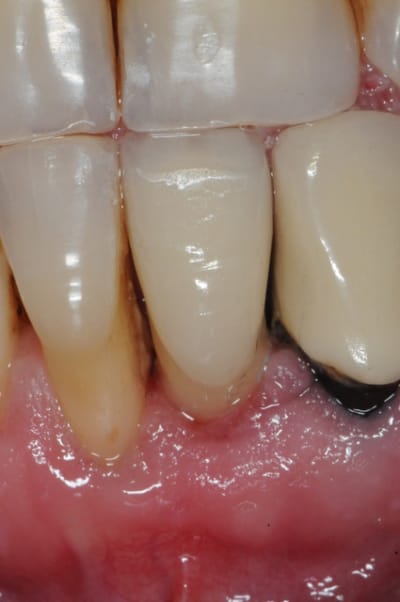

et ici ?? vous feriez quoi ?

32 et 42 pas mobiles

malheureusement, l'espace est réduit pour mettre deux implants.

comment avez vous déjà géré ce type de cas ??

le haut est déjà traité...

Img 0064 fykvs7 - Eugenol

Img 0066 bpmgnj - Eugenol